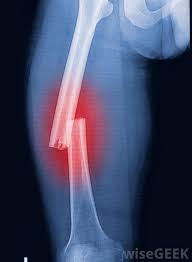

Coalescence of fractures The treatment of fractures and docking with different ways, depending on the degree of elevation or runny blood to Bone, and the bone around, and on the degree and location of the injury, and the age of the patient, and finally on Method of treatment used. Broke the bone always mean poor blood rod to the bone, and all the blood disorder and Rhode impedes Bone healing process and his tackle, while the vigor and vitality of blood vessels is one of the Are essential in the ossification process, so heal shin bone rectangular be While weak heal immediately basal parties bone, the area responsible for the divisions (Cellular bone) because they are rich vibrant, and not through the periosteum, which coats the bone Through the joint, ligaments, tendons close it. The Albanian cell to maximize (docking) formed on the surface of the broken bone, and the bone Soft (sponge) have covered the surface is very large, while the bone hoarder "Extreme coherent" be limited exclusively in the lining of the spinal cord channel Central, and moreover Valazm soft (sponge) is best fed with blood, Therefore, the adhesion is faster than the bone-ROM (Compact). Stages of fusion breakage This should be taken into account when assessing the treatment period, the total blood flow torrent In one of the broken fragments greatness femoral neck or wrist greatly prolongs the period of bone adhesion. Coalescence fractures in X-rays The congestion is caused by the bloody break. During the twelve days is subject to congestion For a particular system. In this period, the movement of the bone fragments can be observed, while appearing in X-sharp cracks or simple fractions and after the process of absorption of tension fabric shows Connective Alaltahami in the case. The initial docking of bone that occurs in the bone tissue contains fragments of Hydroxy Ibnat, and appears in the X-chips such as wool (wool yarn). The parties to the bone Not sharp, and appear on the form of fog (in young people, this show within a few days, and in the Adults from three to four weeks). Biology (vital), the docking marrow appears on the X-like spongy bone, Clearly seen on the bone rectangle. Adhesions and bony take place within three to six months, however, the notch Fractional could occasionally seen after a year and a half, such as those after the duration, or when it happens Total docking bone again, the place where the fracture completely disappear. The information listed are only guidelines for the importance of, and the legal task it requires Preparation and special care to determine the injury, and the date of occurrence and offal. Fusion of skeletal fractures and cured in adults requires anchor calendar limited Time periods (and preventive treatment) as follows: Alazmamdh type of installation Shoulder The upper part of the radius bone The lower part of the radius bone Body of radius Crank (one bone) (Crossbones) The neck of the femur Femoral trochanter area The lower part of the thigh The upper part of the leg Shin The lower part of the leg Ankle area 3 - 5 weeks 4-5 weeks 4-6 weeks 8-10 weeks 6-8 weeks 10-12 weeks 12-16 weeks 8-10 weeks 10-12 weeks 8-10 weeks 10-16 weeks 10-16 weeks... Physiological fusion fractures Congestion of the blood vessels, which Ttglt during 6-8 hours injury arises. And thrombosis associated with a broken bone operates as an intermediary for the proliferation of new cells in the cells Connective tissue between the bone fragments and to form the nucleus of the maker of the new bone. In the early days Following the break, there is the connective tissue between the bone fragments, then quickly show tissue Cicatricial Or granular. In the next stage, and on the newly formed blood vessels, Precipitate Constituent of bone material (a bag skeleton) and produces the so-called bone coherent, and means This phase fragments touch Article initial fusion (Callus) broken bones Such as clinical skeletal Union, which requires several periods, based on the type and size of the bone. In the next phase of treatment, the Albanian cell absorption of bone leads to the replacement Coherent bone bone Mussafah which relates to the composition of lines and load pressure forces the bone ( Afford it). The method described in the docking marrow take place under certain conditions. For Example: the weakness of the installation process (splinting) and complications of Osteopathic installation not only be Seriously annoying, but thus provide adhesion and bone formation detailed false (false - contact Bony placebo). This, and the pollution and inflammation and infection of the fractured bone can disrupt his tackle for a month or Years, so Shell docking marrow contaminated process takes longer. The treatment of fractures requires taking into account the conditions of several chemical and biological tissue, and mechanical ... Although fractures calendar of important things for a sports person to be able to practice his sport. Coalescence fractures disorders Atrophy of skeletal Statistics class, especially in cases of shrapnel fractional surface, be A natural evolution in Alaltahami bone to break. The Sodic exhibitors from serious complications Which affects the mobility and strength of the foot. In the first phase there are complications on the base of Food effect of the nerves in the form of swelling and redness of the skin phenomenon. The X-rays show atrophy skeleton Patchy (only). If the development of the condition continues The symptoms persist, it could get inflation bony tissue Hyper plastic bone)) . Delay or absence of significant adhesions in the complex process of docking skeletal complications. Late adhesions take its place with the continuity of Osteopathic installation (Immobilization) appropriate and proper re-installation of the parties and the broken fragments of bone, and During the X-spacing ends parties bone fracture and a widening fissure fractional show. Late adhesions can be docking in the case of the decay of the bone and his over-zealous, but this The phenomenon of the decomposition of bone and Triqgaha accompany these cases. Can false joint between the parties to the fracture configuration, and this is in the case of decay or not Appropriate reconstructive methods (internal and external reasons). Ray image shows a lack of docking Marrow, rotated gradually, forming a typical bone fracture parties. And the closure of channels Medullary bone marrow and widening fissure, and be detailed false instead of docking Bone and roughly the bones of his relationship thigh and upper arm bones of the hand does not exceed And foot. The emergence of a clear increase in packets of tartar to the parties to the broken bone and gradual closure Channels medullary bone cortex and weak interaction and the widening fissure bone fracture zone All of which give a clear diagnosis for late adhesion false detailed composition process. Unfortunately, it is very natural to be delayed for a change in the course of the case, which reached To injury. On this diagnosis in cases of difficult situations need to be applied imaging And X-rays glass to clarify the situation. Applied Imaging despite foggy and installation of barrier marrow, they illustrate well how and expansion The ends of the broken bone rigid (Sclerosis). Pictures magnifying able to give details More pronounced for the installation of the bone, and the restoration of the bone on the other hand. As a result of individual injuries, Accompanied by multiple fractures, can be accompanied by muscle calcification after infection, and in varying Different because of the rupture of the cortex bone fragments fractures, and muscle brachial gibbet of the most Muscles prone to calcification.... Calcification of bone can be seen above the extrusion coronal (calcification appear hazy and then Take the form Osvenjia). As can be seen above the muscle calcification trigonometric and muscle widening Inside the femoral. Tissue calcification and encircles the full shift (caught) connective tissues Overlapping parts of the muscle. Such calcified muscles appear in radiology through 3-5 Weeks, and increase to 6-8 months after infection. The access to these complications The barriers are very important, because it reveals early on calcified muscle. Chronic fractures These cases are caused by continuous endurance excess bone, working on excessive resistance Physiological, and ease of occurrence minute, especially sports-related (fractures injuries Debilitating or tired from areas prone to increase endurance, such as second and third paragraphs And fourth paragraphs of cervical, and foot and thigh, with the exception of the inner surface of the femur The trachea and heels). In many cases, fractures can not can not see the incision in X, and this explains the rich fusion and interaction in the bone cortex (periosteum), and if you take Image rays early, it can be seen clearly notch. Detailed false Pseudoarthrosis This consists in the place of the fracture, which was due to some reasons the parties do not coalesce with fracture Each other. After two or three months in place of the fracture, and rather than be docking Bone, cartilage tissue consists of (brittle) and this will be detailed and placebo. In such cases, Valjrahh is the only treatment, and this is made up in the following points: 1. Remove the configuration cartilage 2. revive the edges of the parties fractures and bone using pruning. 3. Action landing install metal (osteosinthesis). Pruning is taking bone marrow crust of the leg area of the young upper area Bone (epiphysis). And digging long channel between naughty and pen bone fracture is placed in the stream Channel, and this usually proves Palmthbtat cuneiform metal. User injured and edger placed in broken install Gypsum for 3-6 months. If an event in Milan Another axis of the bone and beyond any growth after surgical intervention, there is no objection from another surgical intervention To evaluate the warp winning, and an amendment bone (osteotomy). And here takes into account the length of Lists The infected patient, out of fear of what the Palace. Many scientists believe that the reasons for the false joint occurrence lies in hormonal factors affect the Metabolism of the components of the bone on top of calcium, as well as the softer bone Acquired in some people. Sudeck's atrophy of bone: It is the demise of mineral salts from the infected bone opposed, and loss of elasticity of the soft tissue Surrounding the fracture, as a result of poor blood circulation, especially in the articular region prone To infection. He spoke these symptoms in most cases in the joints of the lower limbs and the attendant Status radiating pain in the affected area, and poor circulation as a result of tight blood (Vasoconstriction) happens after the paralysis of the puppet aneurysm (vasodilation) In the case First blood vessels shrunken (Mnaqbdh) and cellular poor nutrition while in case The second blood Valawaah expansive and slow speed of blood flow and the recent result is One. And that the deficit in the cellular nutrition results are: 1. demise of bone mineral salts. 2. The loss of elasticity of the soft tissues. 3. Muscular Dystrophy. These variables are a serious impediment occur if preventive therapeutic methods are not followed to prevent Evolution. We can consider the offer Sodic paralysis of the blood vessels and pass this projector in three stages Succession: The first stage: the stage of pain and swelling hinge called the acute phase. Second stage: the stage of racial decomposition of metals and leachability of the bone. Third stage: the stage of continuity and decay metal salt of the bone (change structure Bone). The clinical picture of the situation: Articulated radioactive pain in the affected area, swelling and swelling, Redness of the skin, chilled articular region, and infect a cold sweat and movement painful articular And limited. The surrounding soft tissue atrophy in the case of the occurrence of articular stiffness. Therapeutic intervention: The therapeutic intervention varies from one person to another due to varying degrees of injury among persons Therapeutic accurate and interference in stages and its application. And it must take the following steps: - Lack of detailed Qbarp (violent) motor. - Hinge installation does not give satisfactory results. - Kinetic applied by the processor should be under the limits of pain, because this can Cause atrophy. - The application of therapeutic support and active movements that depend on the patient. - Repeated several times a day therapeutic movements. - Raise the physical ability when injured. - The use of water means (water treatment) and electric therapy in the treatment of the case.